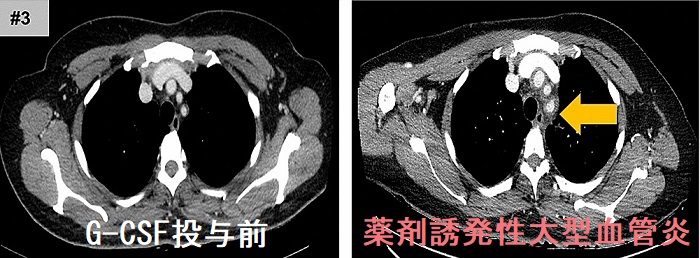

甲状腺機能亢進症/バセドウ病治療薬、抗甲状腺薬(メルカゾール、プロパジール、チウラジール)の最も恐ろしい副作用である無顆粒球症(好中球という白血球が激減し免疫不全におちいる状態)には、G-CSF(顆粒球コロニー形成刺激因子)製剤を投与します。G-CSF製剤の重大副作用に薬剤誘発性大動脈炎(薬剤誘発性大型血管炎)があり、大動脈炎症候群(高安病)と画像上似ているため鑑別を要します。[G-CSF(顆粒球コロニー形成刺激因子)製剤と甲状腺](Mod Rheumatol Case Rep. 2020 Jan;4(1):74-78.)

(薬剤誘発性大型血管炎 造影CT画像 Sci Rep. 2020 Oct 29;10(1):18647.)